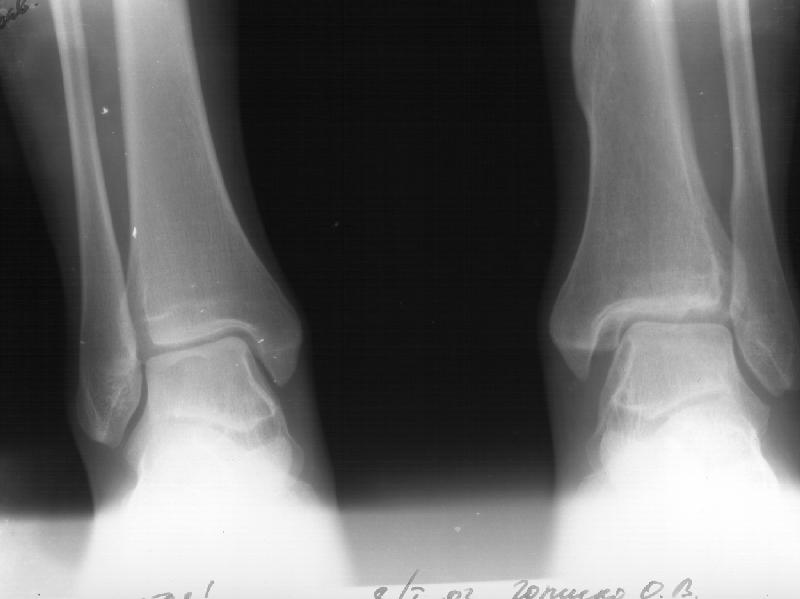

Девочка 14 лет полтора года назад оперирована в детской больнице по поводу спирального перелома костей голени (снимок 1)- выполнен закрытый остеосинтез стержнем Богданова, введенным ретроградно с медиальной стороны (снимок 2). Фиксатор после сращения удален

(см. снимки 3 и 4, после удаления, для сравнения со здоровой стороной, фас - стоя с нагрузкой на обе ноги). В настоящее время беспокоят боль и отеки в области голеностопного сустава при нагрузках, после ходьбы. В покое и ночью боли нет. Амплитуда движений в голеностопном суставе практически полная. Имеется заметная боковая нестабильность, т.е. несостоятельность дельтовидной связки и межберцоого синдесмоза. Складывается впечатление, что при остеосинтезе был отколот и смещен в сторону сустава костный фрагмент позади внутренней лодыжки, увеличилось смещение отломка заднего края, что привело к столь ранним проявлениям деформирующего артроза. Встает вопрос - что делать сейчас? Артодез - наверно, рано. Ревизию сустава, моделирующую резекцию? Пластику связок? Что-то еще? Заранее спасибо.